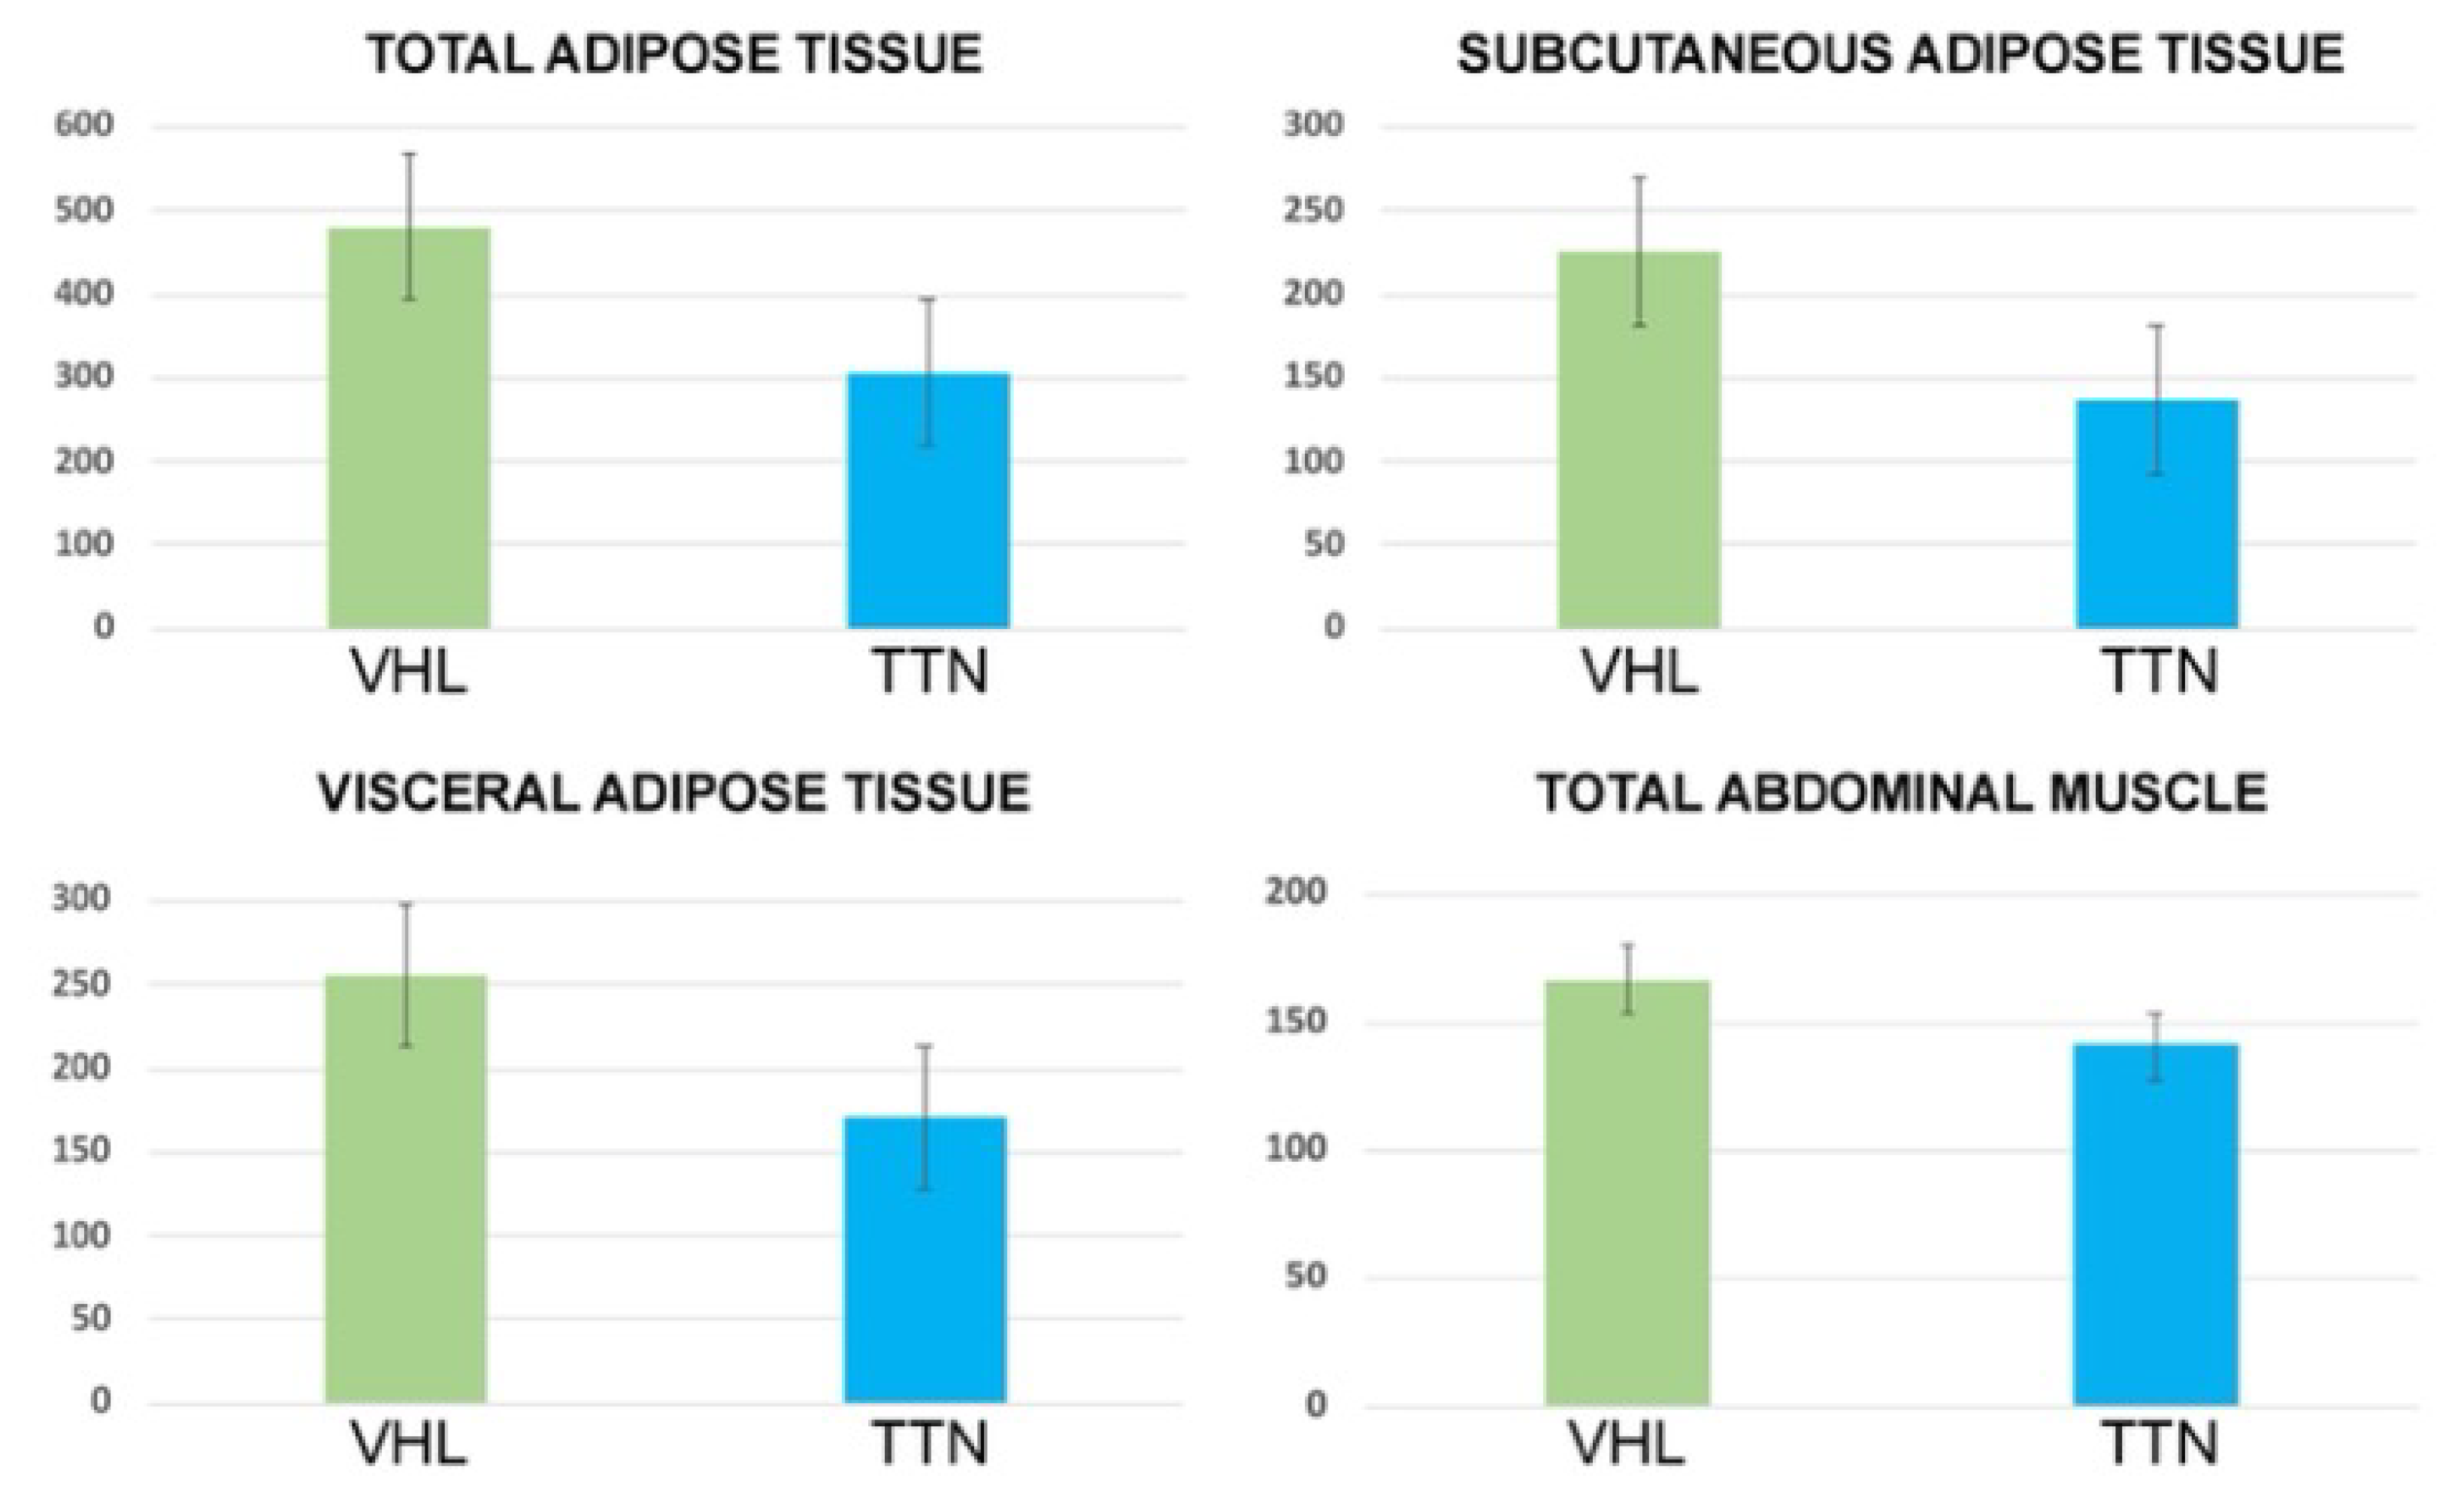

3.2. Body Composition

| TAT Area (cm2) | VAT Area (cm2) | SAT Area (cm2) | TAM Area (cm2) | VAT/SAT Ratio | |

|---|---|---|---|---|---|

| ccRCC-VHL group (mean, range and standard deviation) | 479.8 158.7–914.7 200.5 | 254.4 40.7–505.1 113.6 | 225.3 64.6–632.1 119.6 | 166.8 76.3–219.2 32.2 | 1.2 0.3–2.7 0.6 |

| ccRCC-TTN group (mean, range and standard deviation) | 305.8 97.3–583.8 150.8 | 169.5 18–410 110.6 | 136.3 66.7–280.4 57.8 | 140.9 91–200.5 30.7 | 1.2 0.2–2.3 0.6 |

| p | 0.005 | 0.02 | 0.01 | 0.01 | 0.7 |